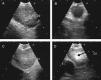

Figura 2.Series de imágenes ecográficas de EBUS de ganglio linfático mediastínico que muestran diferentes criterios (continuación). A)Presencia de estructura hiliar central (flecha) en linfadenitis reactiva. B,C)Presencia de estructura hiliar central con vaso sanguíneo (flecha) en otro ganglio linfático reactivo; demostración en modo Doppler en C. D)Margen mal definido con ecogenicidad heterogénea en metástasis extratorácica con ausencia de estructura hiliar central.